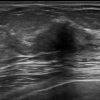

Ung thư vú

» Thông tin: Nữ giới – 76 tuổi.

» Lâm sàng: Khối tuyến vú.